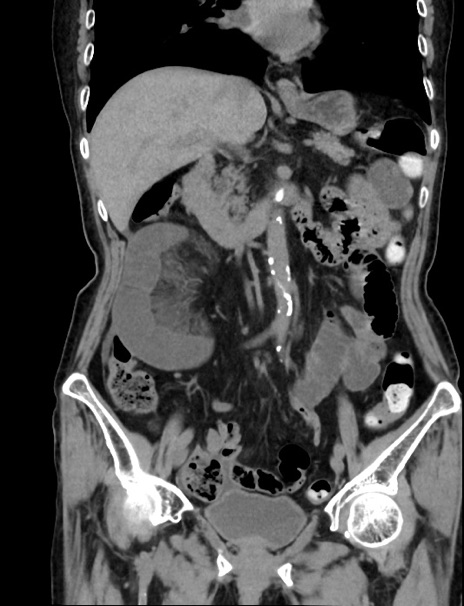

症例33(冠状断像)

【症例】70歳代 女性

【主訴】心窩部痛

【現病歴】延髄病変の精査・加療にて神経内科入院中。本日より心窩部痛あり。

【身体所見】右下腹部を中心に圧痛と反跳痛あり。

【データ】WBC 10900、CRP 0.02